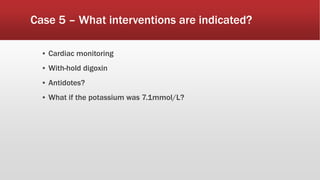

This document discusses various cases of collapse and syncope. It defines collapse as transient loss of consciousness with loss of postural tone and full recovery. Syncope is defined as loss of postural tone with or without loss of consciousness and full recovery. It then discusses the multiple potential causes of collapse and syncope including toxicological, cardiac conduction abnormalities, structural cardiac issues, autonomic dysfunction and more. It then goes through 9 case examples, discussing important questions to ask, potential tests and interventions for each case.